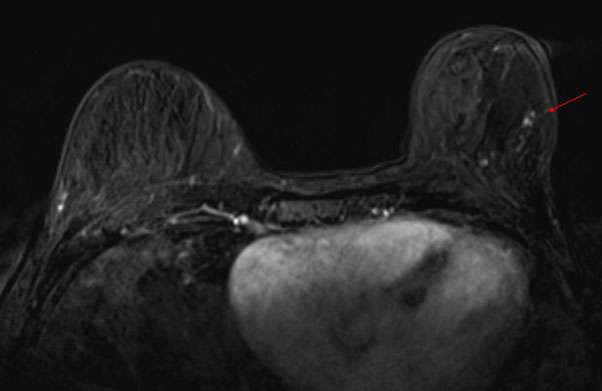

Case: Paget's Disease Figure 4

Figure 4: Contrast enhanced breast MRI of the same patient demonstrates linear non-mass enhancement in the upper outer quadrant of the left breast. MRI guided biopsy yielded an additional site of cancer.